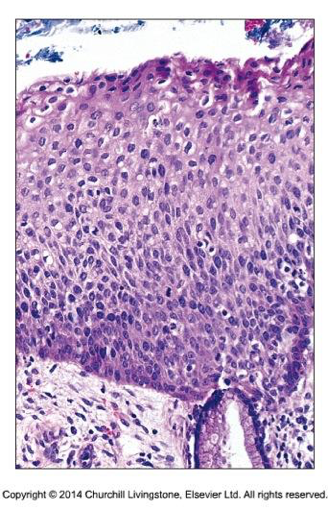

Histopatologi: Morfologin vid HSIL ses som en proliferation av atypiska keratinocyter, med ökad kärnstorlek, oregelbundna kärnmembran och ökad kärn-cytoplasma-ratio, med förekomst av mitoser, även atypiska (Fig PAT-2). Vid HSIL, tidigare CIN2, finns atypiska celler i högst 2/3 av skivepitelet (Fig PAT-2, översta 2 bilder), och vid HSIL, tidigare CIN3, finns atypiska celler ut i yttre tredjedelen av skivepitelet (Fig PAT-2, nedersta bild). Mitoser ses ofta i mellersta och/eller ytliga tredjedelen av epitelet.

Figur PAT-2: Histologi av HSIL. De första två bilderna visar gränslesioner som i det tidigare systemet kallades CIN2 [6].

Bilaga 7. 4.1 Figur3.pngBilaga 7. 4.1 Figur4.png

Bilaga 7. 4.1 Figur5.png